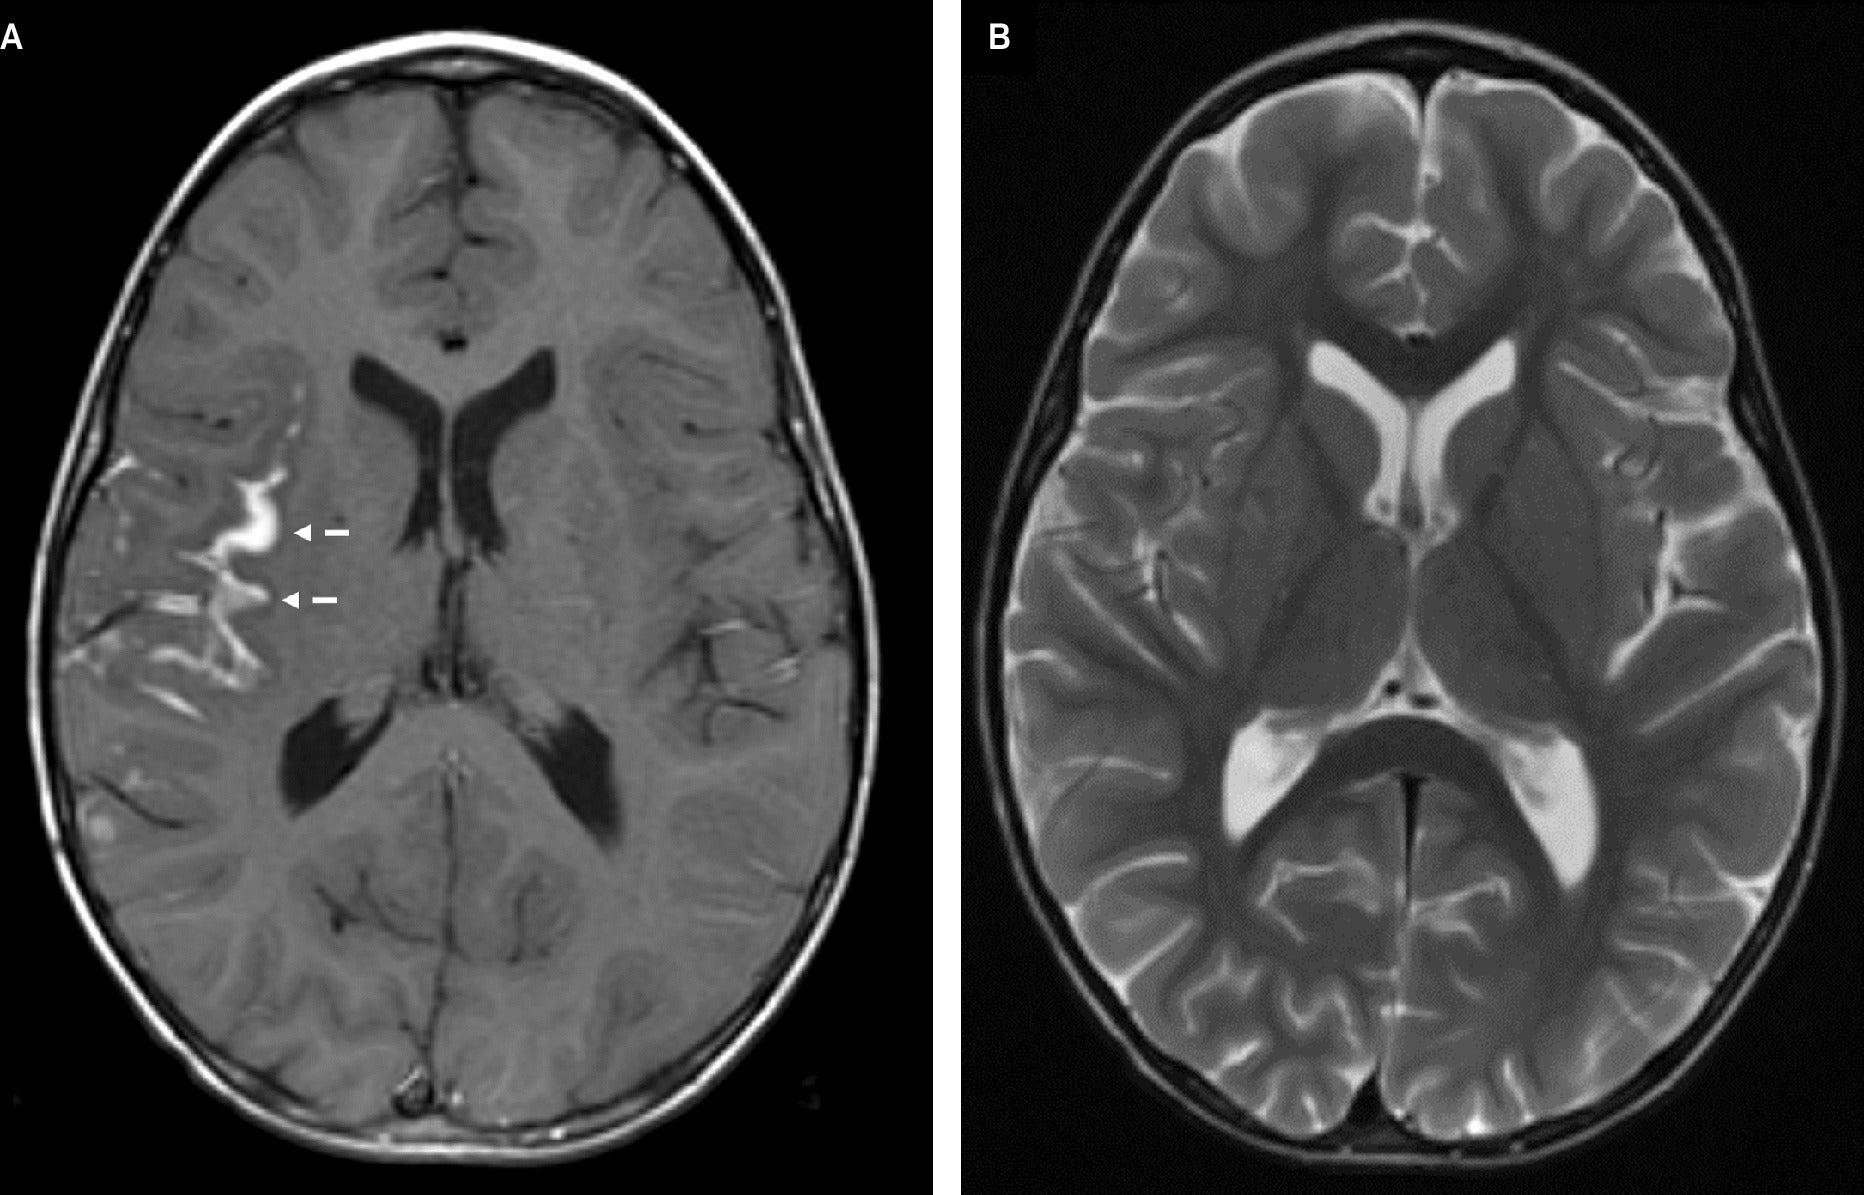

Cerebral magnetic resonance imaging (MRI) ( Figure 1 ) demonstrated signal abnormality in the Sylvian fissure along the insular cortex. No significant vasogenic edema was noted. Cranial computed tomography (CT) ( Figure 2 ) obtained 19 days later showed an interval increase in the extension of the hyperattenuating lesion in a gyriform distribution, at this time also involving the right frontal lobe, allowing for the differences in modalities between studies. A follow-up MRI obtained 7 days after the CT demonstrated a mass-like lesion with gyriform distribution, markedly increased size, and significant surrounding vasogenic edema, consistent with worsening leptomeningeal disease ( Figure 3 ).

A post-contrast axial gradient-echo T1-weighted image (A) demonstrates gyriform enhancement in the deep Sylvian fissure, most pronounced along the insular cortex (dashed arrows). The corresponding axial turbo spin echo T2-weighted image (B) demonstrates no significant surrounding parenchymal vasogenic edema. The lesion is not easily visible on this sequence.